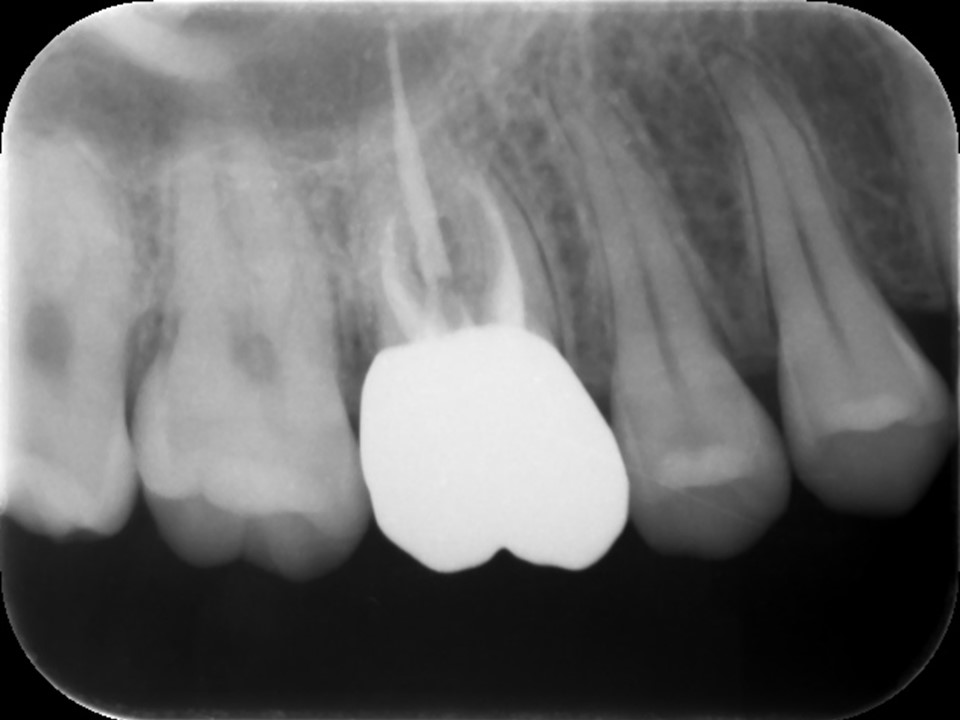

Case4

薬が根尖に届かず再発のケース

図1、術前レントゲン | 図2、 根管充填後レントゲン |

![]() |

図1、根管治療が不十分で白い薬が根尖(歯根の先端)まで届いておらず、根尖部に歯槽骨の吸収による黒いレントゲン透過像を認める。我が国の保険の根管治療はこのような例が非常に多いです。

図2、根尖部まで隙間なく緊密に薬が詰まっているのが分かる。正しく根管治療を行えば、溶けて吸収した歯槽骨は数か月程度で再生してきます。